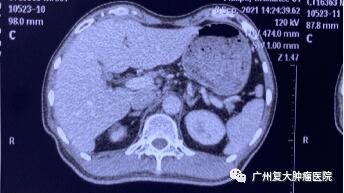

影像圖片顯示

圖3

為求進(jìn)一步診療,2020年11月,患者來(lái)廣州復(fù)大腫瘤醫(yī)院就診。入院完善相關(guān)檢查發(fā)現(xiàn):CA-199指標(biāo)高達(dá)2289u/ml(CA-199屬胃腸道腫瘤相關(guān)抗原,是一種腫瘤標(biāo)志物,正常值≤37u/ml);肝實(shí)質(zhì)內(nèi)有多個(gè)結(jié)節(jié)狀,較大者約4.3×3.8cm。胰腺體、尾部均有腫塊,并鄰近腸管、脾靜脈局部粘連不清,大小約4.3x3.3cm。